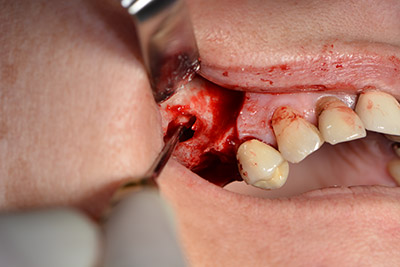

Operatives Vorgehen beim Implantieren

Die klassische Schnittführung (krestal, Entlastung bukkal) und das Präparieren des Mukoperiostlappens erlauben eine gute Übersicht.

In diesem Fall werden Sky Implantate (bredent) verwendet, deren chirurgisches Protokoll die Pilotbohrung mit etwa 1.200/min vorschreibt (Abb. 9).